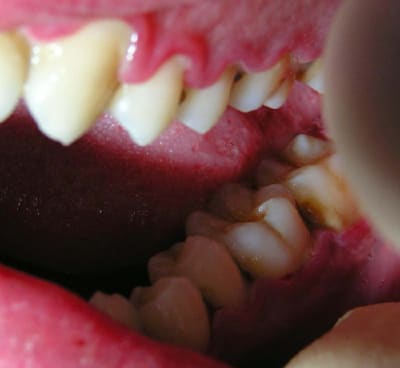

J'ai ressorti les photos prises initialement:

22/06/2005 à 02h01